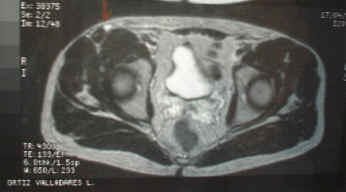

Se procede a estudio de TAC y Resonancia Magnética. para posterior evaluación.

Buena evolución a las 48 horas. La flecha deja ver los restos de la cola de la colección aspirada y difundida hacia el celular subcutáneo, por el vendaje compresivo. ( imágen de Resonancia Magnética )